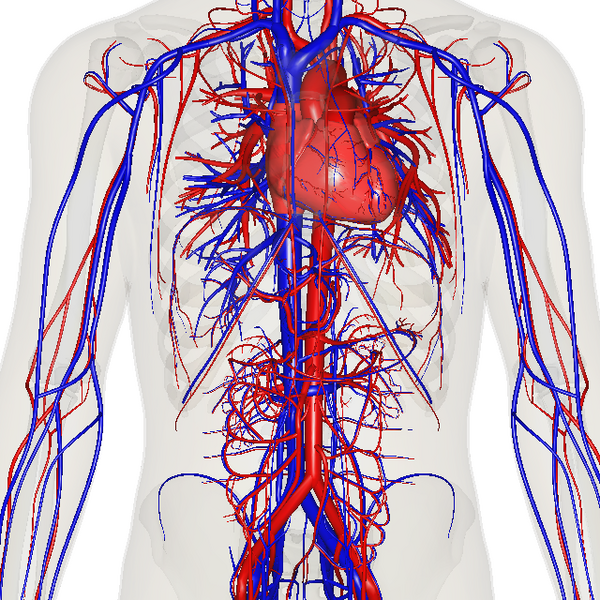

Циркуляторная система, также система кровообращения и кровеносная система [1]система органов, включающая сердце, кровеносные сосуды и кровь, которая циркулирует по всему телу человека или другого позвоночного[2][3]. Включает в себя сердечно-сосудистую систему (также кардио-васкулярная система от греческого kardia — сердце, и латинского vascula — сосуды), которая состоит из сердца и кровеносных сосудов. Кровеносная система состоит из большого и малого круга кровообращения[4].

Сеть кровеносных сосудов составляют магистральные сосуды сердца, включающие крупные артерии и вены, другие артерии и артериолы, а также капилляры, впадающие в венулы (мелкие вены), и другие вены. Кровеносная система у позвоночных замкнута, это значит, что кровь никогда не покидает сеть кровеносных сосудов. Некоторые беспозвоночные, такие как членистоногие, имеют открытую систему кровообращения. У диплобластов, таких как губки и гребневики, кровеносная система отсутствует.

Система кровообращения включает сердце, кровеносные сосуды и кровь[3]. Сердечно-сосудистая система у всех позвоночных состоит из сердца и сосудов. Кровеносная система делится на два основных контура — малый и большой круги кровообращения[2][4]. Малый круг кровообращения представляет собой контурную петлю от правого желудочка, по которой кровь поступает в легкие, где она насыщается кислородом и возвращается в левый желудочек. Большой круг кровообращения доставляет насыщенную кислородом кровь от левого желудочка к остальной части тела и возвращает кровь обратно в правый желудочек через крупные вены, известные как полые вены. Циркуляцию крови также можно разделить на две части — макроциркуляцию и микроциркуляцию. В среднем у взрослого человека содержится от пяти до шести литров крови, что составляет примерно 7 % от общей массы тела[9]. Кровь состоит из плазмы, эритроцитов, лейкоцитов и тромбоцитов . Пищеварительная система также работает совместно с системой кровообращения, обеспечивая организм питательными веществами, необходимыми для поддержания работы сердца[10].

К кровеносным сосудам относятся артерии, вены и капилляры. Крупные артерии и вены, несущие кровь к сердцу и от него, известны как крупные сосуды[14].